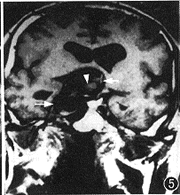

例2 男,38岁。复视,右眼视力下降半年。外院诊断颅咽管瘤,来本中心求治。体检:右外展神经麻痹,右眼视力0.8。CT平扫(图3):鞍旁4.0 cm×3.0 cm×5.0 cm高密度占位,右侧裂内1.0 cm×0.8 cm×1.0 cm高密度占位,边界清,周边呈蛋壳样钙化。MRI示鞍区、鞍上混杂信号占位,边界清,内有流空信号和不同强度短T1、长T2信号,周围脑组织受压水肿(图4,5)。MRA示右颈内动脉蛇形血管通道,累及右大脑中和大脑前动脉(图6)。DSA示右颈内动脉自岩段起呈蛇形迂曲扩张, 累及右M1、A1段及右后交通动脉,血管通道内血流缓慢,静脉窦期仍见对比剂滞留(图7,8)。右颈内动脉球囊闭塞加强试验阴性,但交叉代偿循环充盈试验阳性,先行右颞浅动脉-大脑中动脉搭桥术,术后24 h内,右颈外动脉造影显示吻合口通畅,遂行载瘤动脉近端球囊闭塞术,载瘤动脉闭塞后右颈外动脉造影显示通过吻合口的血流增加(图9)。术后1年随访,症状、体征消失,生活工作正常,CT复查:瘤周脑组织水肿消失,大小无明显变化。

图4 MRI T2WI,鞍上占位(↑),病变内不同时期的血栓(Δ),见流空效应、占位效应和脑水肿

图5 MRI T1WI,示鞍上、右鞍旁分叶状占位(↑),病变内不同时期的血栓(Δ),见流空效应和占位效应